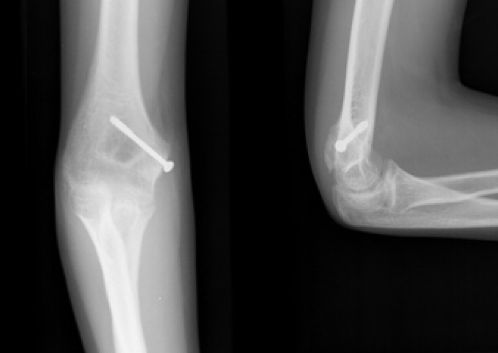

Figura 8: a-d, Imagen radiografica de fractura del cóndilo lateral con desplazamiento articular. Tratamiento quirúrgico mediante reducción abierta y osteosíntesis.

Figura 9: a: Fractura de epitróclea asociada a luxación de codo. b: Reducción abierta y osteosíntesis con tornillo.